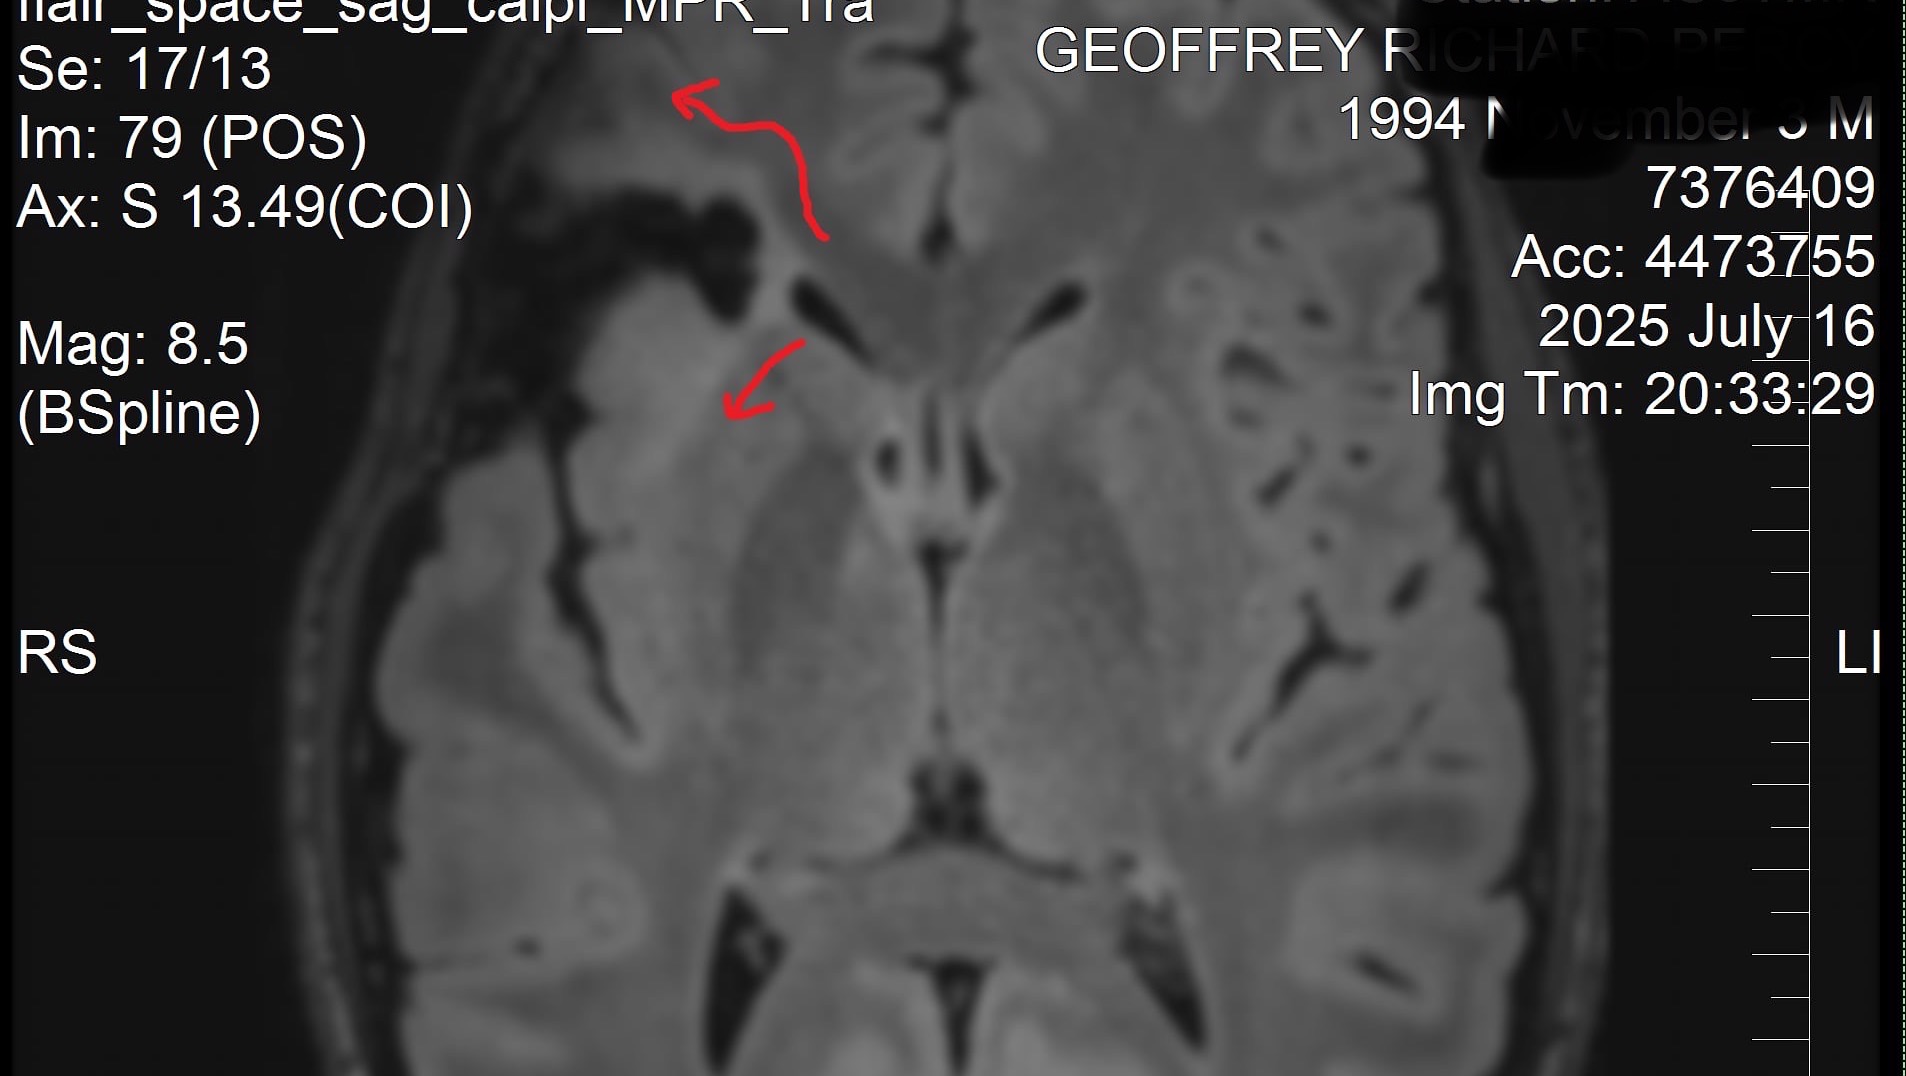

Hi, my name is Ashley we need help for my best friend Geoffrey who 4.5 years ago was diagnosed with a grade 2 oligodendroglioma. He needs funds for medication called Vorasidenib to help prolong his life. This medication costs thousands a month as it is not on the PBS. Let me tell his story. Oligodendrogliomas are rare primary brain tumors that develop from oligodendrocytes, cells that support and insulate nerve fibers. They are a type of glioma, which are tumors that originate from glial cells in the brain. They are uncommon in younger men, and Geoffrey was 25 when diagnosed. His first oligodendroglioma was surgically removed. It had been growing there for a long time. It was able to be fully resected.

Geoffrey has now had a recurrence of oligodendroglioma, grade 2, possibly grade 3, UPDATE!!!! GOOD NEWS GUYS ITS GRADE 2! FOUND OUT 24/09/2025 !! this time in a deeper part of the brain in an area where it cannot all be surgically removed. Geoffrey has just had his second brain surgery successfully and is recovering. It was a maximum resection and not all was able to be removed.